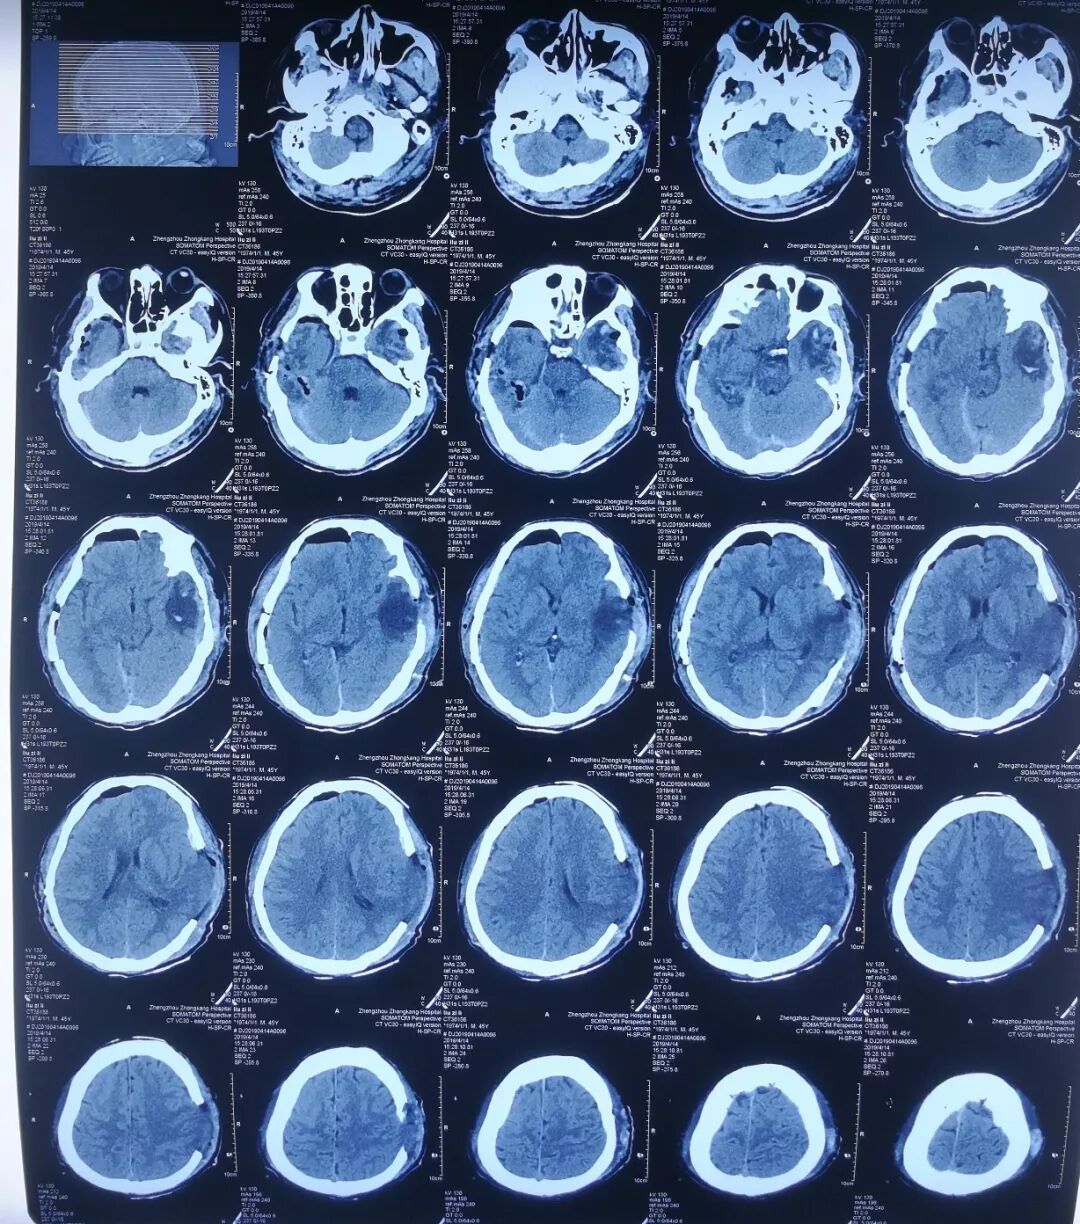

2019年4月11日凌晨,周口鹿邑县的刘某因车祸严重撞击,出现多处出血,陷入昏迷状态。随后被收治到郑州中康医院(原新密市红十字中心医院)。经医院检查诊断,刘某发生蛛网膜下腔出血、多发脑挫裂伤、左侧硬膜外血肿、颅骨骨折、头皮血肿、头皮撕脱伤等情况,属重型颅脑损伤,同时伴有肺挫裂伤。由于其伤情比较复杂、颅脑创伤严重,必须马上行开颅手术。

入院时刘某头颅CT